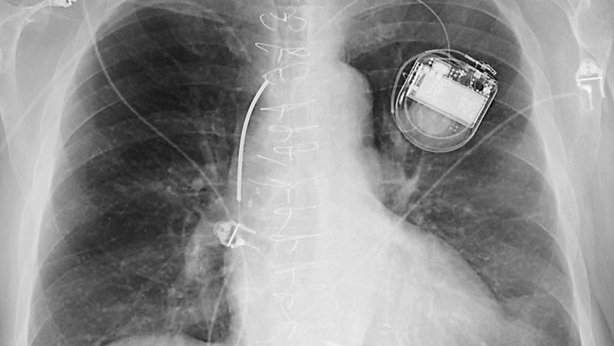

Infarto es cuando una parte del tejido del órgano cardíaco

muere por falta de irrigación de sangre. Si el área afectada fue grande, las

secuelas serán más complejas. También afecta el grado de enfermedad coronaria

que se posea y el estado de las arterias.